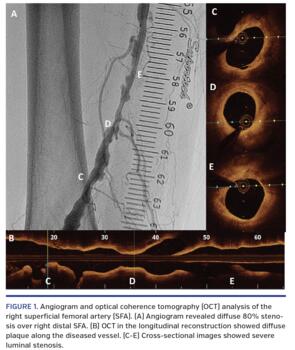

The HawkOne directional atherectomy system (Medtronic Peripheral) was used to restore blood flow by removing plaque. After placing a 7 mm SpiderFX device (Medtronic Peripheral), optical coherence tomography (OCT) was acquired to assess baseline plaque load (Figure 1). Several runs of directional atherectomy were done. Angiogram and OCT were then obtained to assess the result of directional atherectomy (Figure 2). Drug-eluting balloon was applied afterward. The final angiographic result was excellent. A 3-month course of dual-antiplatelet therapy was given, followed by lifelong aspirin. There was no recurrence of symptoms at subsequent 1-year follow-up.

Vessel dissection following atherectomy or balloon angioplasty is the most common reason for bail-out stenting in the SFA. Yet, the use of stents has several potential shortcomings, including stent fracture. OCT can accurately assess the effect of endovascular interventions to the vessel wall, providing excellent resolution for any presence of microdissections, residual clot, and suboptimal minimum lumen area. A trial has shown OCT-guided atherectomy for femoropopliteal disease to be safe and effective, yet data in the Asia-Pacific population are limited. To the best of our knowledge, this is the first report of OCT evaluation of SFA atherectomy in the Asia-Pacific region. We demonstrate the possible feasibility of this technique in Chinese populations.